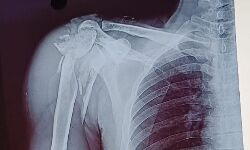

Chhindwara News: सिम्स में सफल ऑपरेशन, मरीज के कंधे की बुरी तरह चूरा हड्डियों को दोबारा जोड़ा

Chhindwara News: मेडिकल कॉलेज से संबद्ध जिला अस्पताल में भर्ती दुर्घटना में घायल एक मरीज के कंधे की हड्डियां आठ से दस हिस्सों में टूट गई थी। मेडिकल कॉलेज के चिकित्सकों की टीम ने कूल्हे की हड्डियों का कुछ हिस्सा निकालकर चूरा हो चुकी हड्डियों की जगह प्रत्यारोपित की। सफल ऑपरेशन के बाद अब मरीज का हाथ पूरी तरह से काम करने लगा है। इस तरह का ऑपरेशन चिकित्सकों की टीम ने भी पहली बार किया है।